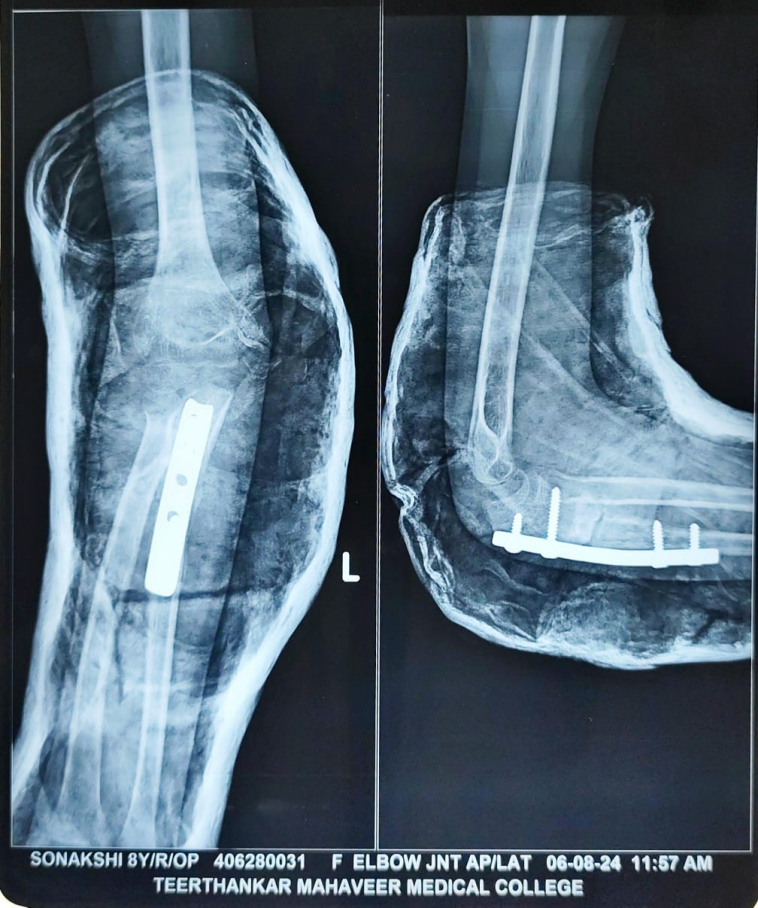

The post-operative course was uneventful. The limb was immobilized in an above-elbow slab for 3 weeks, followed by initiation of a gentle range of motion exercises under physiotherapy guidance. The child was monitored at regular intervals – 2 weeks, 1 month, 3 months, 6 months, 9 months, and 15 months post-operatively (Fig. 4, 5, 6, 7).

Figure 4: 1-month follow-up X-ray.

Figure 5: 3-month follow-up.

At each visit, clinical and radiographic assessments were performed. Over time, the child regained the movement in the wrist and MCP joint extension and thumb extension.

By the 9-month follow-up, radiographs confirmed complete union of the osteotomized ulna, and the radial head remained in a reduced, anatomical position. To prevent any implant-related complications, implant removal was done at 9 months (Fig. 8).